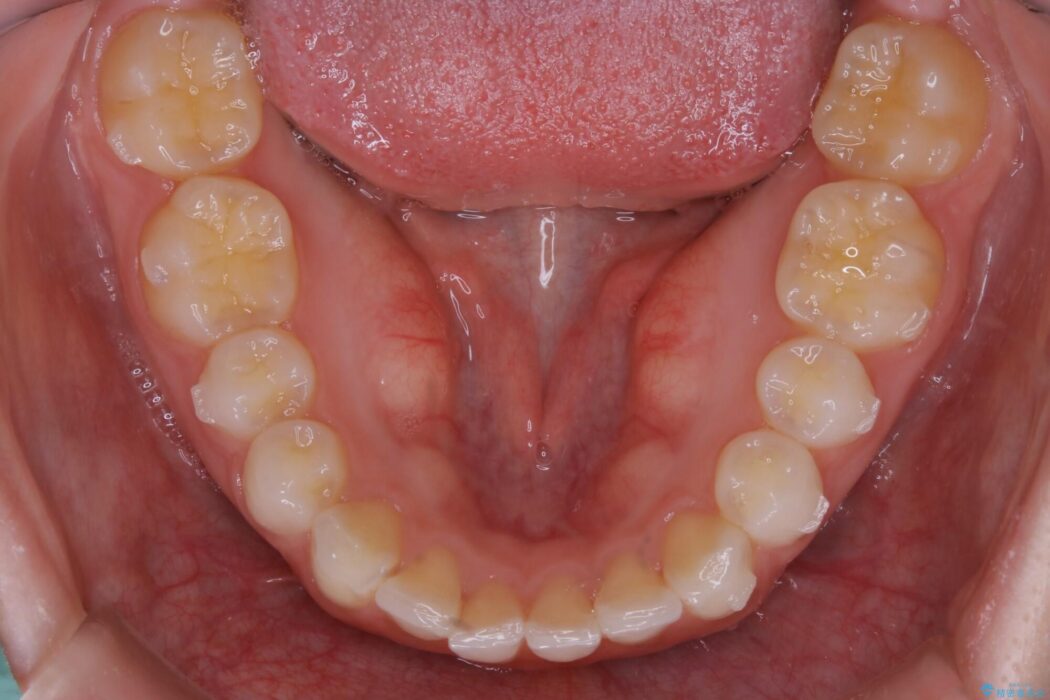

上下前歯のねじれなどで生じている歯列のガタつきをなおしたいとのことで来院されました。

精密検査をしたところ、奥歯に大きな問題がないため移動はほとんど必要がなく、また主訴であるガタつきの改善に必要なスペースも少量であったため、インビザラインのライトパッケージの治療をご提案しました。